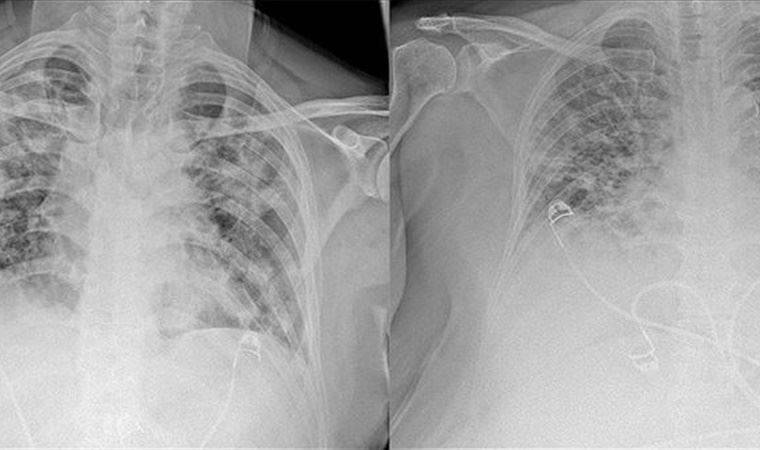

Normal akciğer görüntüleri ile koronavirüs hastalarının akciğer görüntüleri arasında ciddi farklar bulunduğunu belirten Karalezli, şu bilgileri verdi:

"İnsanların aradaki farkları anlamaları için her iki akciğer görüntülerine de yer verdim. Görüntülerdeki beyazlıklar akciğerdeki tutulumu gösteren görüntüler ne yazık ki. Bu hastalar yoğun bakım hastaları. Filmler birbirine az çok benzeyen şekilde. Altta yatan hastalığı olanlarda ise daha kötü seyrediyor."

Kliniğe yeni başvuran bir hastanın, 5 Ağustos'ta çekilen tomografi görüntülerindeki tipik koronavirüs görüntülerinin olduğunu ifade eden Karalezli, hastanın bir hafta içerisindeki tomografi görüntüsünde ciddi değişiklik olduğunu ve enfeksiyonun çok arttığını söyledi.